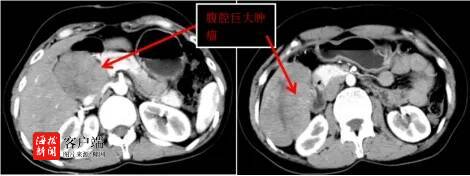

陈女士入院后,肝胆胰外科给她进行了详细的检查,发现陈女士此次病情相较于上次更加严重。肿瘤与多个重要脏器紧密相邻,压迫肝门,侵犯肝脏组织,并且包绕重要血管,治疗难度非常大。考虑到陈女士情况紧急,高良辉主任立即组织了多学科会诊,并根据会诊建议,为患者进行了肿瘤穿刺活检,明确肿瘤性质,以便进一步治疗。

3月5日,肝胆胰外科宋奇锋副主任医师为陈女士施行了腹腔肿瘤血管造影栓塞术。次日,高良辉主任为陈女士进行了剖腹探查+腹部滤泡树突状细胞肉瘤切除+肝6段切除+胆囊切除+粘连松解,术中出血较少,手术耗时3小时15分钟。术后,陈女士很快就康复了。